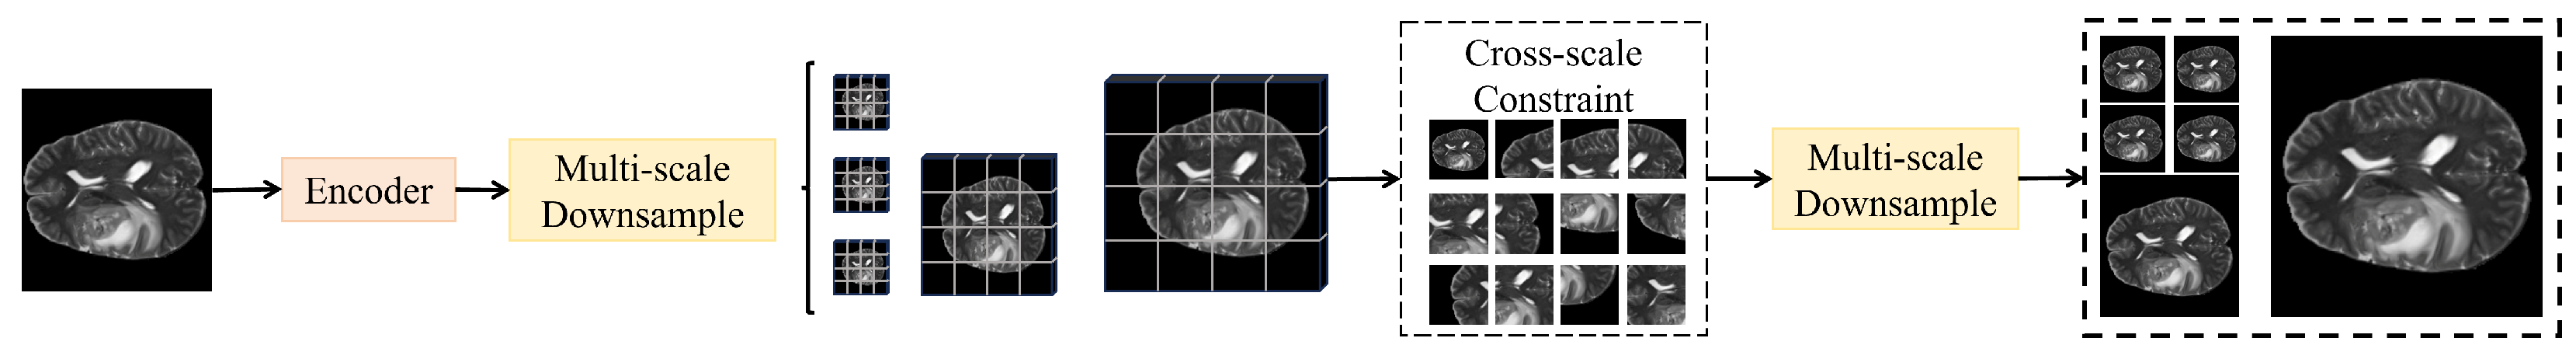

3.3.4. Cross-Scale Consistency Constraint Module

The cross-scale consistency constraint module is designed to address the inconsistency problem among predictions at different scales, ensuring that segmentation results maintain semantic and boundary coherence across multi-level outputs. As shown in Figure 4, this module operates directly on the multi-scale predictions generated by the decoder, where , , , , and denotes the binary segmentation mask channels.

Figure 4.

Illustration of the cross-scale consistency constraint module.

The core idea of the module is to establish coordination between local and global predictions across scales through bidirectional mapping and consistency constraints. Specifically, a convolution is first applied to project each scale prediction into a unified embedding dimension , followed by upsampling and downsampling operations that align all predictions to an intermediate resolution of , forming the aligned set . At this scale, the cross-scale consistency loss is introduced:

where indicates the number of scales. This loss enforces convergence of predictions within the embedding space toward a consistent distribution, thereby mitigating prediction fluctuations and boundary misalignments caused by scale discrepancies. Furthermore, to enhance boundary-level consistency, a boundary consistency term is defined as

where ∇ represents the Sobel operator used to extract boundary gradients of the predicted masks. This constraint ensures that boundaries across different scales preserve similar contour shapes, thereby improving stability in small lesions and blurred boundary regions.

The module consists of two major sublayers: the scale alignment layer and the consistency constraint layer. The scale alignment layer comprises convolution and bilinear interpolation, with channels unified to 64, while LayerNorm is applied to high-level features to guarantee numerical stability. The consistency constraint layer employs a combination of cosine similarity correction and Euclidean distance penalties to prevent prediction collapse into overly smooth distributions. To reduce computational overhead, loss calculation is restricted to a sampled point set S with a sampling ratio of , which can be theoretically regarded as a Monte Carlo approximation of full-pixel consistency. Its unbiasedness guarantees that the expected sampled consistency constraint equals the global constraint, i.e.,

thereby proving that no systematic bias is introduced by sampling. When combined with the local detail attention module and the global context attention module, this module ensures that fine-grained and global semantic enhancements provided by the former are further consolidated by scale-consistent convergence at the output level. The overall optimization objective is formulated as

where is the primary segmentation loss, and are balance coefficients. Mathematically, this design is equivalent to introducing a convex consistency constraint into the multi-scale prediction space, thereby maintaining topological stability across scales. When applied to medical imaging tasks, the module significantly reduces the drift of small lesion predictions across levels, producing final fused results with sharper boundaries and enhanced cross-domain robustness, with particular improvements in Dice and IoU metrics.